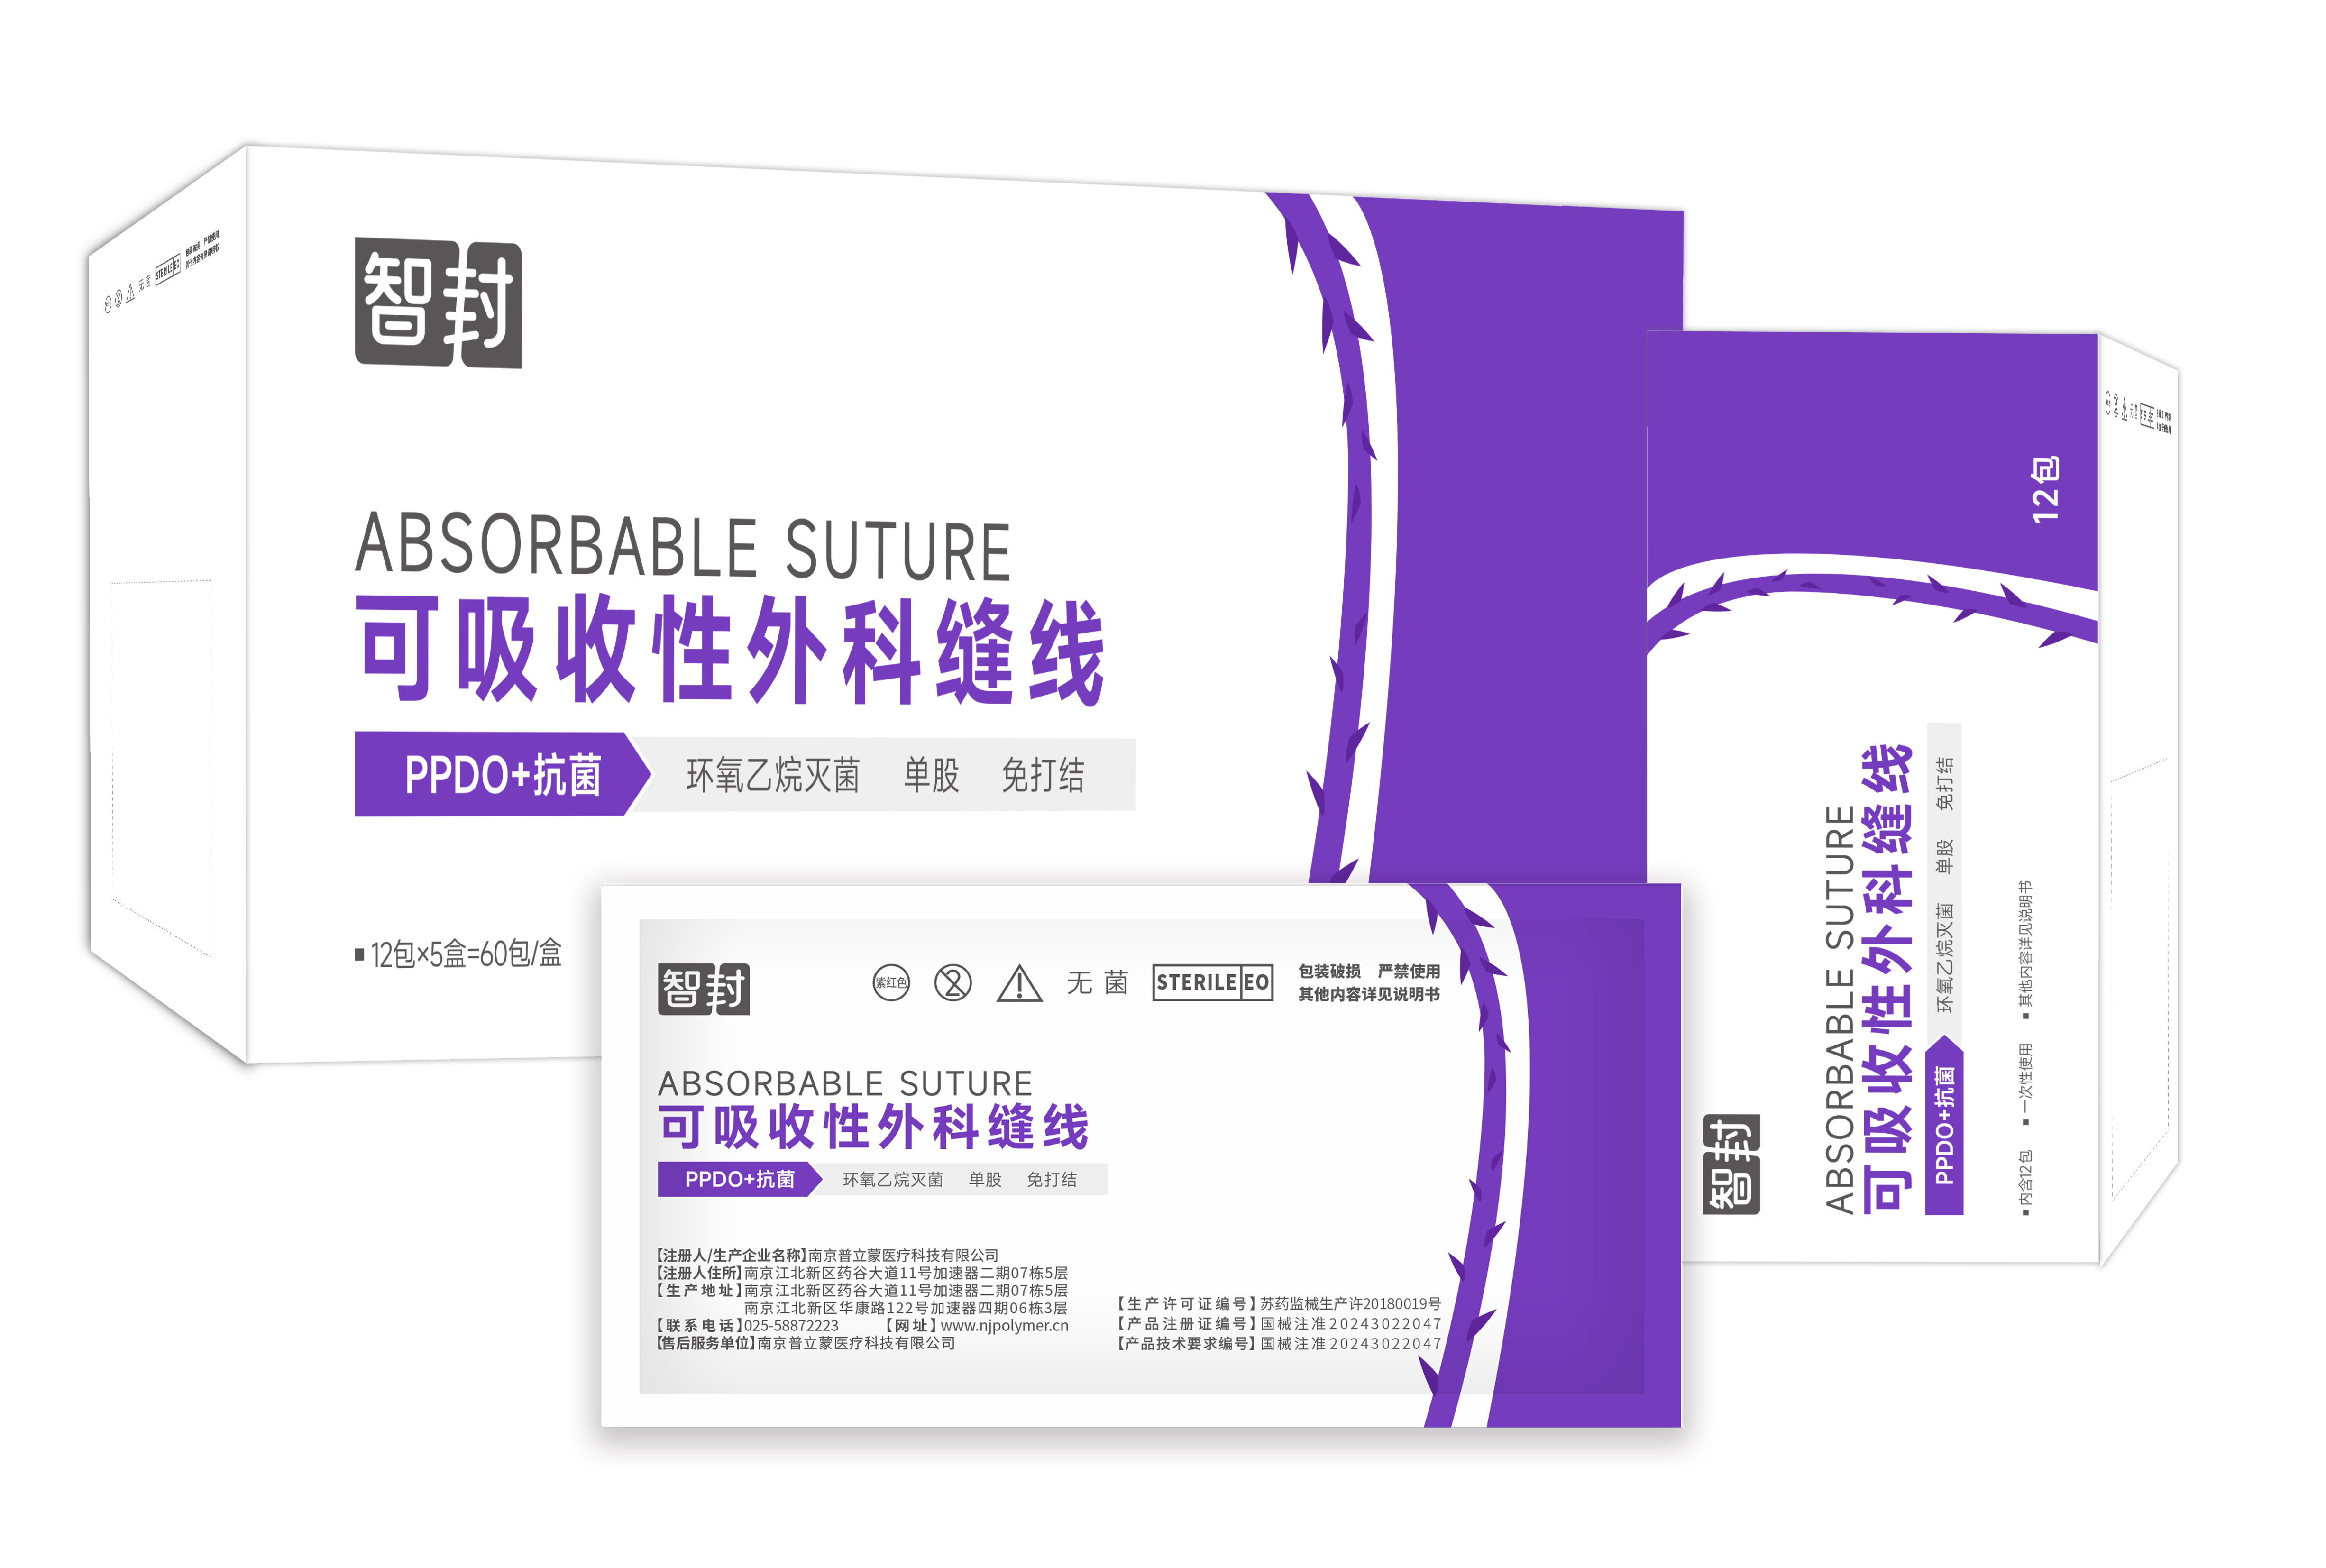

我们的产品

立足于全国市场,适应客户的变化需求。追求提供更加快速,高效,安全,紧密的解决方案。

可吸收性外科缝线(自封)-PPDO可吸收性外科缝线(自封)-PPDO进口原材料,规格丰富 PPDO,可吸收全水解 自主研发、最新倒刺切割技术 倒刺设计,缝合免打结 安全性高,缝合疤痕小

可吸收性外科缝线(自封)-PPDO可吸收性外科缝线(自封)-PPDO进口原材料,规格丰富 PPDO,可吸收全水解 自主研发、最新倒刺切割技术 倒刺设计,缝合免打结 安全性高,缝合疤痕小 -

可吸收性外科缝线可吸收性外科缝线

可吸收性外科缝线可吸收性外科缝线 -